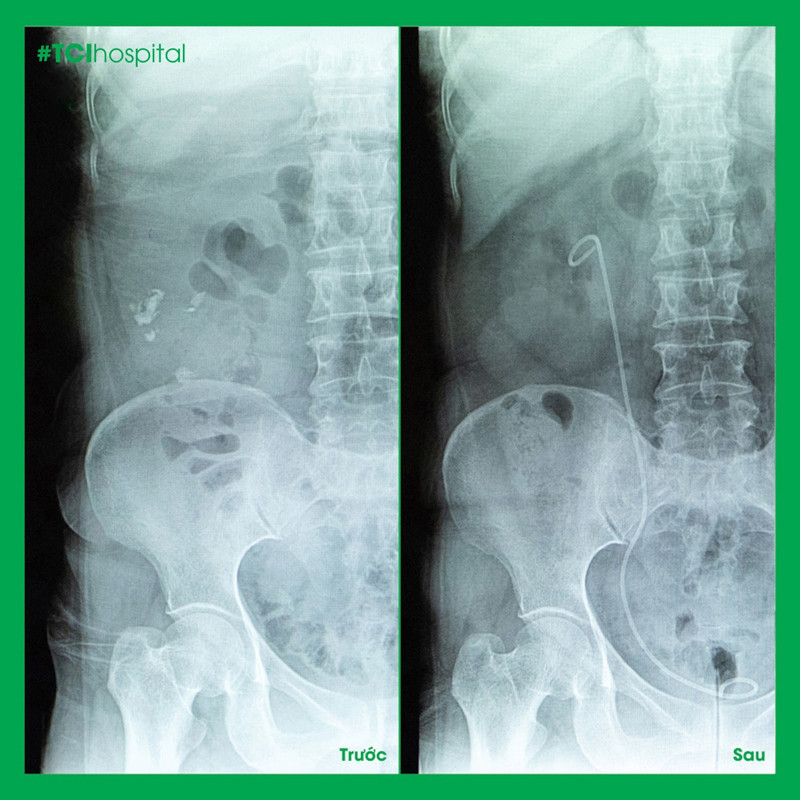

Tán sỏi ngược dòng loại bỏ hoàn toàn sỏi niệu quản 1/3 dưới của bệnh nhân N.T.M

Bác N.T.M sau khi được tán sỏi niệu quản chia sẻ: “10 năm trước tôi từng mổ sỏi thận, đến giờ nghĩ lại vẫn còn sợ. Lần này tán sỏi ở Thu Cúc rất nhẹ nhàng, không cần mổ, đang tán sỏi mà tôi ngủ quên lúc nào không biết. Lúc tán xong cũng không có cảm giác đau, khoảng 3 ngày sau là tôi đã sinh hoạt như bình thường”.